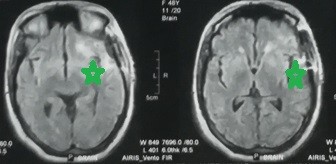

A huge meningioma at the base of the skull on the left side, extending into the temporal lobe and part of the frontal lobe, compressing the optic nerve, carotid artery, and left median artery. It clearly compresses all parts of the left hemisphere of the brain. It was completely removed without any significant brain problems, as shown by the radiographs in the follow-up four months after the surgery. The 50-year-old patient was suffering from persistent headaches, seizures and visual impairment. The patient is in very good condition and is going about her life as usual.